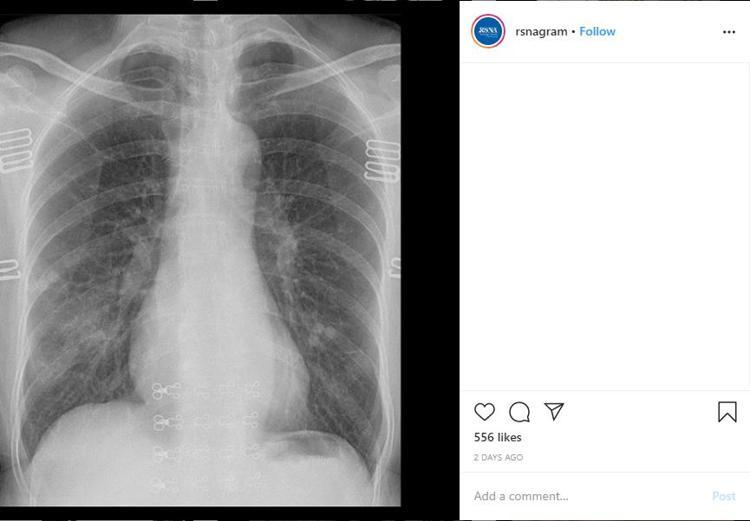

Son Dakika Haberi Korkunc Gercegi Corona Virusu Nden Olen Hastanin Rontgeni Ortaya Cikardi En Son Haberler

www.hurriyet.com.tr

44 Yasinda Corona Virusten Hayatini Kaybeden Kisinin Akciger Rontgen Filmleri Virusun Verdigi Zarari Ortaya Cikardi Saglik Haberleri Ntv

www.ntv.com.tr

Son Dakika Haberi Korkunc Gercegi Corona Virusu Nden Olen Hastanin Rontgeni Ortaya Cikardi Son Dakika Guncel Haberler 11 50

Son Dakika Haberi Korkunc Gercegi Corona Virusu Nden Olen Hastanin Rontgeni Ortaya Cikardi Sondakika Haberler 4 50

Koronavirusu Nden Olen Hastanin Rontgeni Ortaya Cikardi Bursa Hakimiyet

www.bursahakimiyet.com.tr